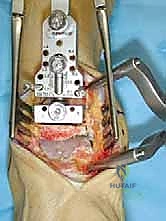

الخطوات الجراحية التفصيلية لزراعة مفصل HINTEGRA

تُجرى العملية عادة تحت التخدير النصفي أو العام، وتستغرق حوالي الساعتين إلى ثلاث ساعات. الدقة هنا تقاس بالمليمترات وأجزاء الدرجة الزاوية.

1. الشق الجراحي والوصول للمفصل

يقوم الجراح بإجراء شق أمامي طولي (Anterior Approach) في منتصف الكاحل. يتم إبعاد الأوتار والأوعية الدموية والأعصاب بعناية فائقة (هنا تتجلى أهمية مهارات الجراحة الدقيقة التي يمتلكها الدكتور هطيف) للوصول إلى محفظة المفصل.

2. إزالة الزوائد العظمية وتحرير المفصل

يتم إزالة النتوءات العظمية (Osteophytes) التي تسبب الألم وتحد من الحركة، وتحرير الأنسجة المتليفة لاستعادة المرونة الأولية للمفصل.